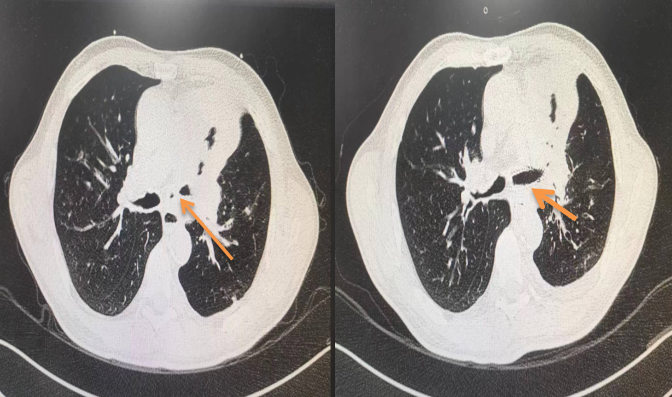

图三 如下图 术前与术后肺部CT对比,狭窄的气道明显扩张